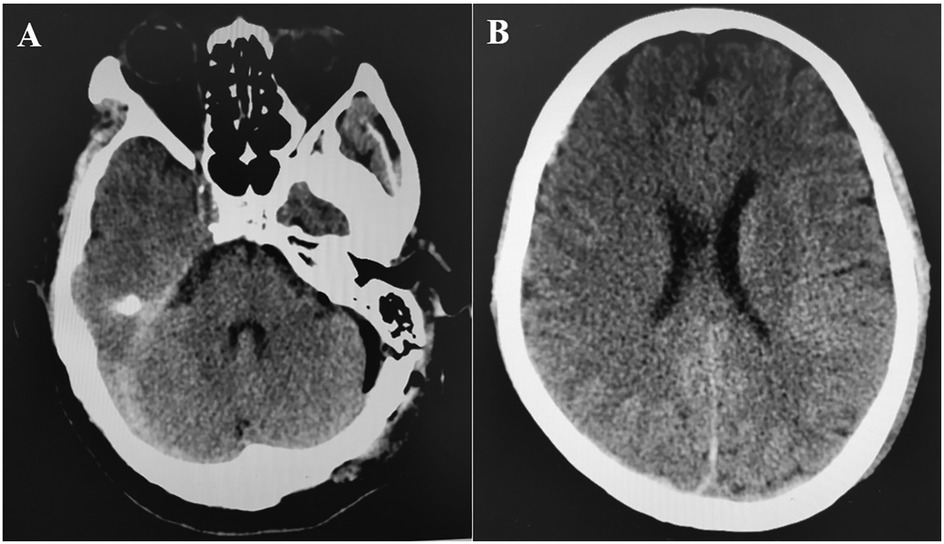

The cause of supratentorial subdural hematoma (SDH) during posterior fossa surgery remains uncertain. However, potential mechanisms include excessive cerebrospinal fluid (CSF) drainage and neck rotation and flexion in the lateral decubitus position (2, 4). Nozaki reported that transitioning patients from the intraoperative lateral position to the postoperative supine position resulted in low intracranial pressure and/or intracranial air, causing the brain to shift and subsequently leading to supratentorial subdural hematoma (6). This hypothesis fails to account for intraoperative bleeding. Recent studies indicate that most subdural hematomas occur on the nondominant side of venous drainage; however, no definitive link exists between venous drainage laterality and bleeding (6, 9). In our case, both the rate and volume of CSF drainage were normal, as previously noted. However, CSF unexpectedly surged from the cistern, which we attributed to increased ICP from the supratentorial SDH, rather than as a cause of it. The hematoma was located on the dominant side of venous drainage (Figure 3), but the relationship between supratentorial SDH and venous pressure remains unclear. Avoiding this rare complication is nearly impossible due to its unknown etiology, and a sudden intraoperative rise in CSF outflow might indicate its occurrence.

Figure 3

MRI scan showing cerebral blood vessels with a focus on the right side. Vessels are highlighted against a darker background, indicating the flow of blood in the brain.

Figure 3. Magnetic resonance venography showed that the left transverse sinus and sigmoid sinus were not visualized, and the venous drainage was mainly on the right side.